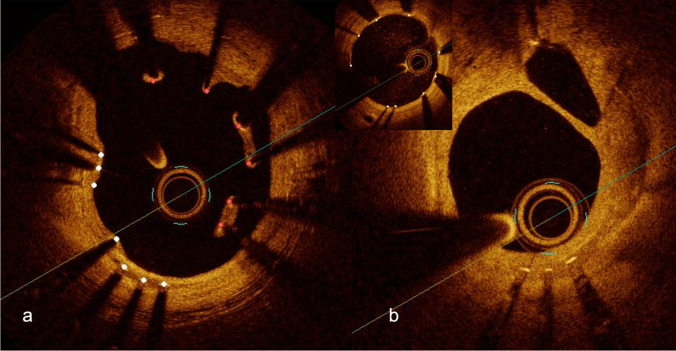

Recent findings: Despite the widespread use of DES and numerous improvements, recent clinical data indicate that ISR still occurs in 5-10% of PCI procedures, posing a considerable public health issue. The incidence, morphology, and clinical implications of ISR are determined by a complex interplay of several factors: the patient, stent, procedure, and vessel and lesion-related factors. Advancements in intracoronary imaging have provided greater insight into its patterns and underlying causes. Over time, treatment strategies have evolved, and current guidelines recommend an individualized approach using intracoronary imaging to characterize ISR's underlying substrate.